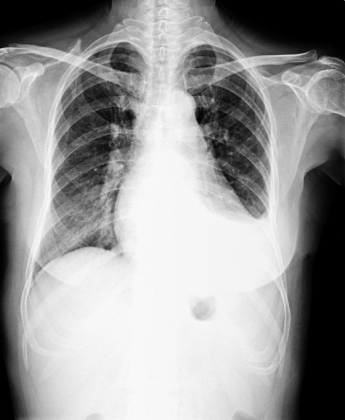

異常胸部X光影像

醫學影像..X光影像